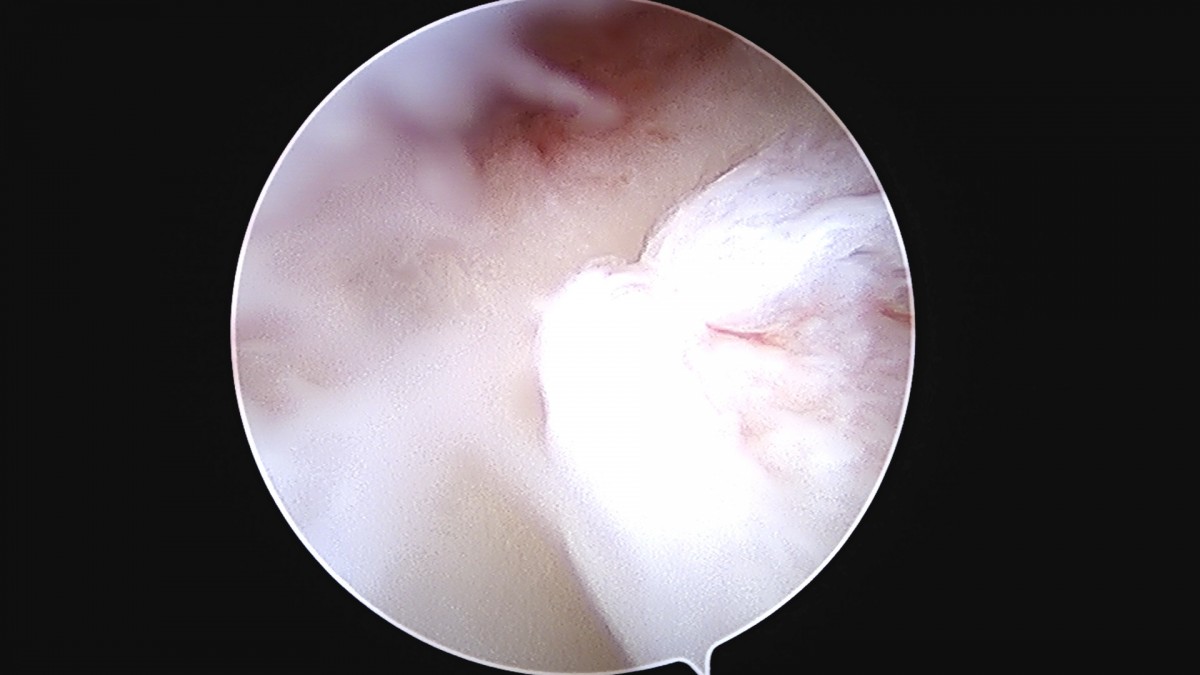

정지영원장님 손목 삼각섬유연골 복합체 봉합술 박현O 환자

dae765e4d9ac96aee867c9d6292d8784_1758009004_2826.jpg